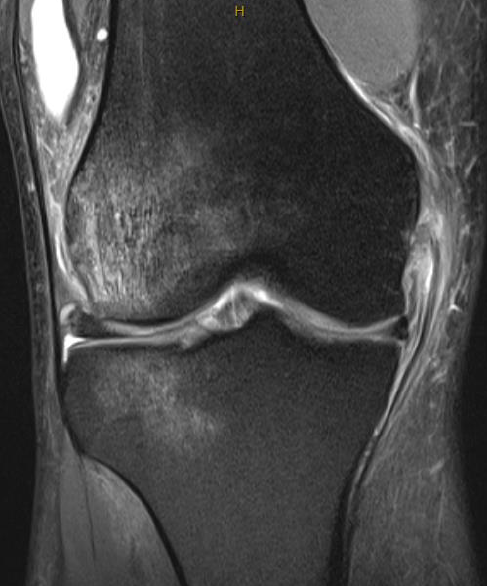

MRI

Classification

Grade I: intact ligament with periligamentous oedema

Grade II: partial tearing with surrounding oedema

Grade III: complete ligament tear

Sites

Femoral avulsion

Midsubstance

Tibial side: wave sign, ensure that the MCL is no flipped above pes anserinus as will not heal (analogous to Stener lesion)

Midsubstance MCL tears

Wave sign indicative of tibial avulsion, with ligament retracted above pes anserinus / hamstring tendons

In the chronic setting see thickening of the MCL